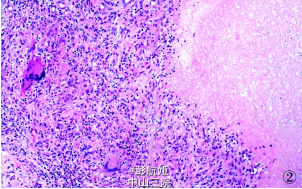

患者男性,39岁。2年前无明显诱因下出现左腕部及手掌红肿伴疼痛性小肿块,自行用针刺破肿块后有清亮或脓性液体流出。遂在当地医院行手术治疗,后肿块再次长大,并伴有左手指麻木,于2011年 员 月到我院就诊。病程中患者无发热、盗汗。专科检查:左手腕部内侧可见鸡蛋大小肿块,背侧见一4cm*2cm*2cm大小条索状肿块,肿块均有压痛及波动感。皮肤表面可见一长约 5cm 的陈旧性手术瘢痕,无红肿及皮肤破溃。否认有结核、肝炎等传染病史,否认有家族遗传病史。术中所见:左腕关节滑囊囊壁与周围组织及肌腱黏连严重,部分肌腱已被侵蚀,囊内含有大量灰白色米粒样物和黄色浑浊液体,部分区域见白色豆渣样物。切除囊壁和清理囊内组织后送病理检查。